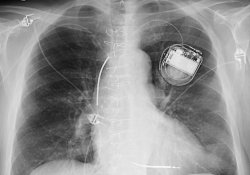

Все больше людей с нарушениями сердечного ритма, в том числе молодых, носят в груди электронные приборы, которые следят за работой сердца и корректируют ее при необходимости. Ученые считают, что приборы отнюдь не препятствуют активному образу жизни.